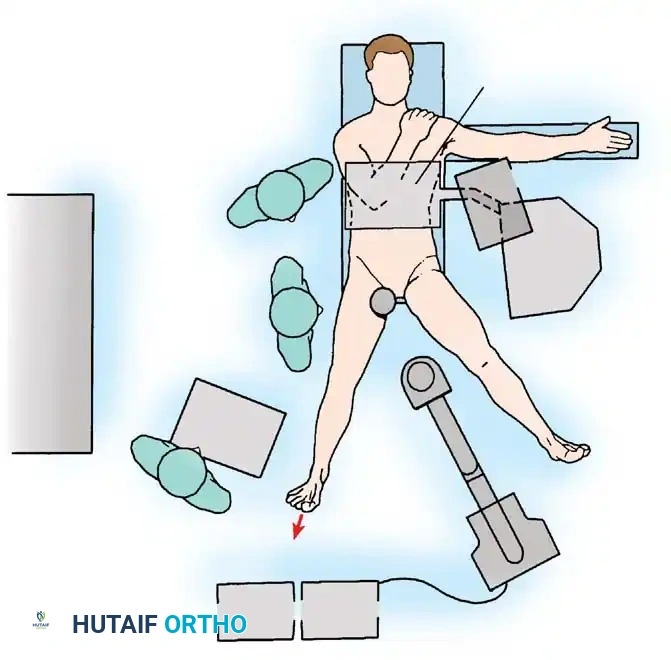

Surgical Technique 48-38: Supine Positioning

- Table Setup: Place the anesthetized patient supine on a specialized fracture table or a dedicated hip distraction system. Ensure complete skeletal muscle relaxation via paralytic agents to minimize the traction force required.

- Perineal Post Placement: Place a heavily padded perineal post, intentionally lateralizing it against the medial thigh of the operative leg.

Clinical Pearl: Lateralizing the perineal post is a critical safety maneuver. It adds a slight transverse component to the traction vector, pushing the femoral head laterally to help break the suction seal, and significantly lessens the likelihood of direct compression and subsequent neurapraxia of the pudendal nerve.

- Limb Positioning: Position the operative hip in extension, approximately 25 degrees of abduction, and neutral rotation.

- Flexion Avoidance: Slight flexion may relax the anterior capsule (iliofemoral ligament) and facilitate distraction, but it places increased traction on the sciatic nerve, drawing it closer to the joint and making it vulnerable to injury. Significant flexion must be avoided.

- Rotation: Neutral rotation is paramount during initial portal placement to protect the sciatic nerve posteriorly, although dynamic freedom of rotation during the procedure aids in exposing different regions of the femoral head and cam lesions.

- Distraction: Apply traction to the operative extremity. Confirm adequate distraction of the joint space fluoroscopically before proceeding with portal placement.